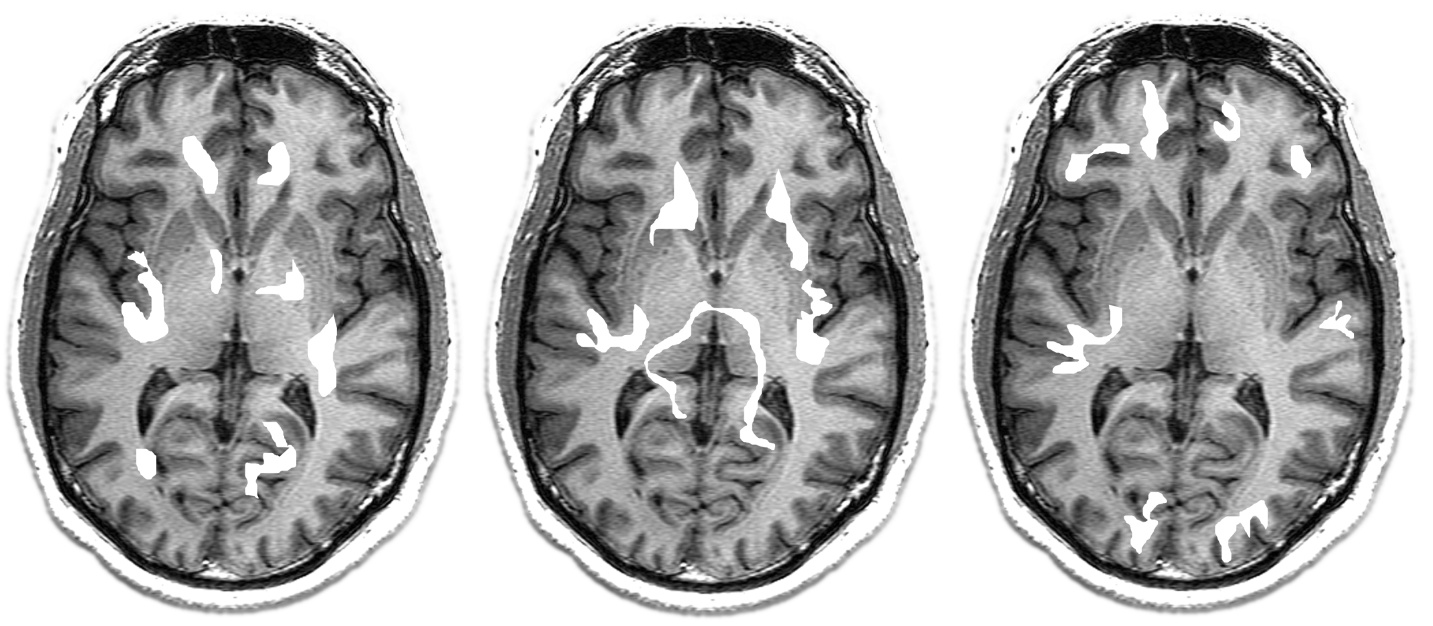

Axial fMRI slices showing activation patterns. The highlighted regions indicate where the BOLD signal has increased β a proxy for neural activity mediated by hemodynamic response. Note the millimeter-scale spatial resolution: individual cortical areas can be distinguished. But these images represent a snapshot averaged over seconds, during which millions of neural events have occurred and been temporally smeared.